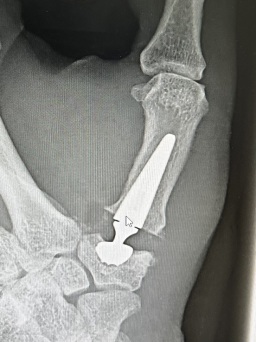

Rhizarthrose / Sattelgelenksarthrose

Die Sattelgelenkarthrose beschreibt einen Knorpel-verschleiß am Gelenk zwischen dem Vieleckbein (Trapezium) und der Basis des

1. Mittelhandknochens. Die ersten Anzeichen treten häufig in Form von Belastungsschmerzen auf, wie z..B. bei alltäglichen Tätigkeiten (Flaschenöffnen, Gläser aufschrauben, Knöpfe öffnen usw.) auf. Zunächst wird konservativ behandelt mit Ruhigstellung einer Orthese, Analgetikatherapie, Spritzen mit Hyaloron oder Eigenblutkomponenten (Plasma, ACP, PRP). Bei Versagen der konservativen Therapie wird die chirurigsche Behandlung empfohlen mit Entfernung des Trapeziums und Bandplastik oder Daumensattelgelenksprothese. Der Eingriff erfolgt in Narkose oder Plexusanästhesie. Nach OP erfolgt eine Ruhigstellung bis ca. 3 Wochen, ggf. Physiotherapie. Wenn eine Prothese eingesetzt wird erfolgt die Ruhigstellung nur wenige Tage. Alltägliche kraftfordernde Tätigkeiten sind in der Regel ab dem 2. Monat nach OP wieder möglich.

Nach Protheseneinbau in unsere Klinik.

Sattelgelenkprothese (Typ:Touch Fa. Medartis)